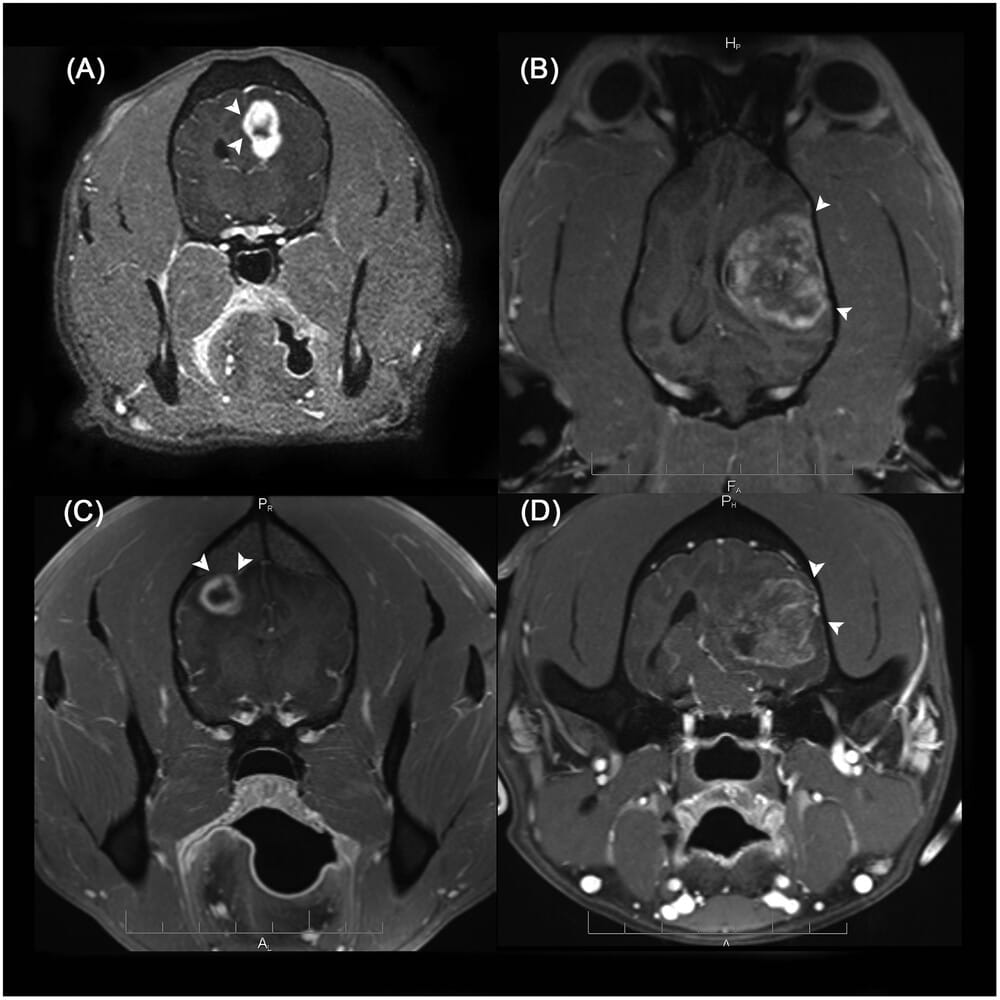

Examples of cases where the “claw sign” was present with strong evaluator agreement. Postcontrast T1-weighted (T1W) transverse image (A), postcontrast T1W dorsal image (B), and postcontrast T1W transverse images (C and D) of 4 dogs with peripherally located, contrasting enhancing glioma. The white arrow heads in A-D point out the acute angle formed with the meninges and thinning of the brain parenchyma. The dogs are a 10-year-old intact male French bulldog with a high grade oligodendroglioma of the left cerebrum (A), a 6-year-old spayed female boxer with a grade III oligodendroglioma of the left cerebrum (B), an 11-year-old spayed female American pit bull terrier with a high grade oligodendroglioma of the right cerebrum (C), and an 8-year-old castrated male boxer with a grade IV astrocytoma (formerly known as glioblastoma multiforme) of the left cerebrum (D). For the cases in A, B and D, all 5 evaluators across both sessions rated them positive for the “claw sign”. For the first session for case C, all 5 evaluators rated the case as positive for the “claw sign”. For the second session for case C, 4 evaluators rated the case as positive for the “claw sign” and one evaluator rated the case as indeterminate.